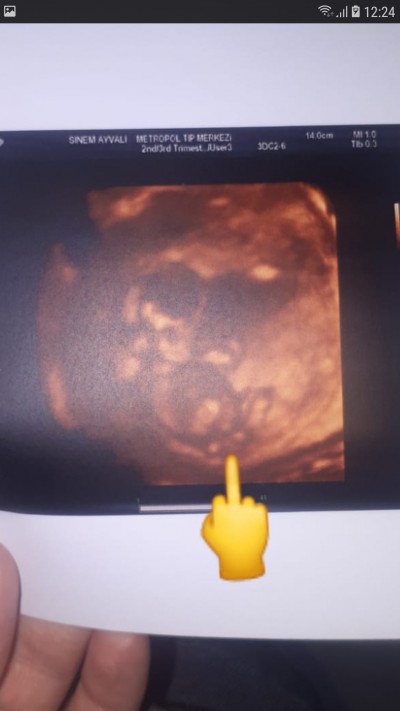

Arkadaşlar doktor söylemedi ortadaki sislik nedir acaba bilen varmı

Göbek kordonu canım  benim bebegiminde ultrasonda boyle var kordon

Göbek kordonu galiba

Kordon gibi cnm bacak arasından yukarda gibi sanki

Ayak o dizlerini bükmuş